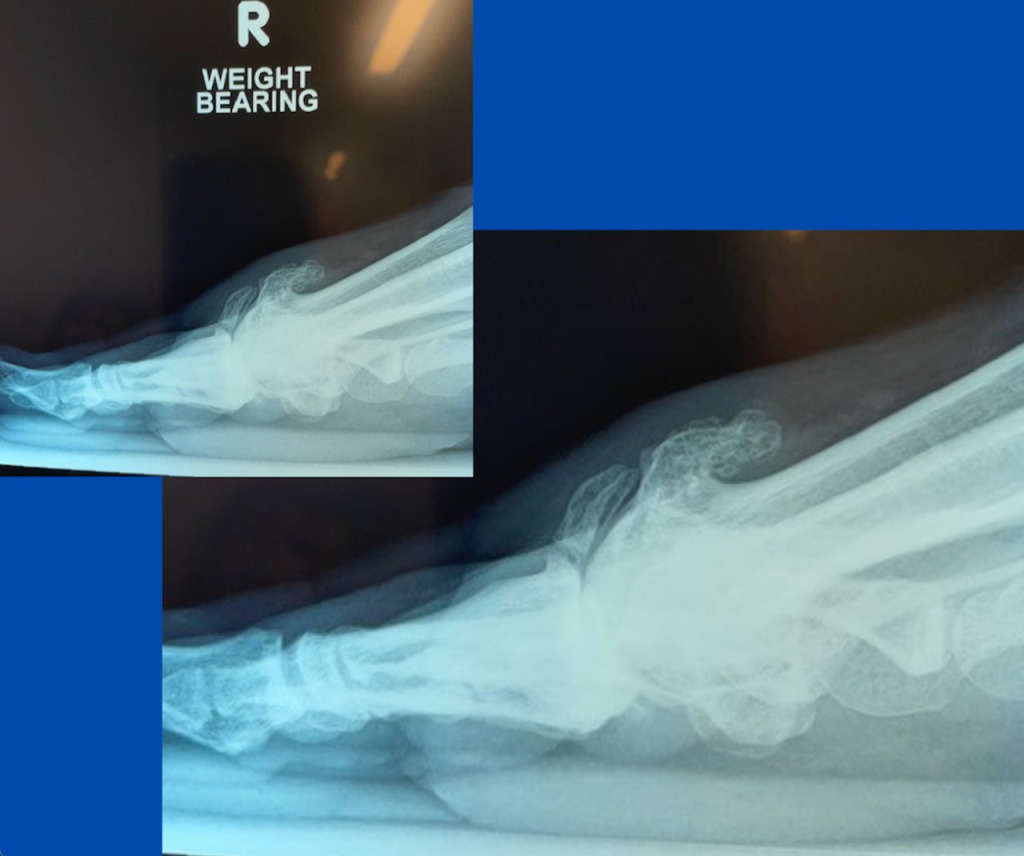

Fractured bone spur

Blog's main page This patient presented in early March with a history of a sudden severely inflamed and painful right 1st MTPJ after a run completed the previous month. The joint became swollen and stiff after the run, and symptoms have slightly settled. The patient has had a generalised ache in the joint for a few [...]